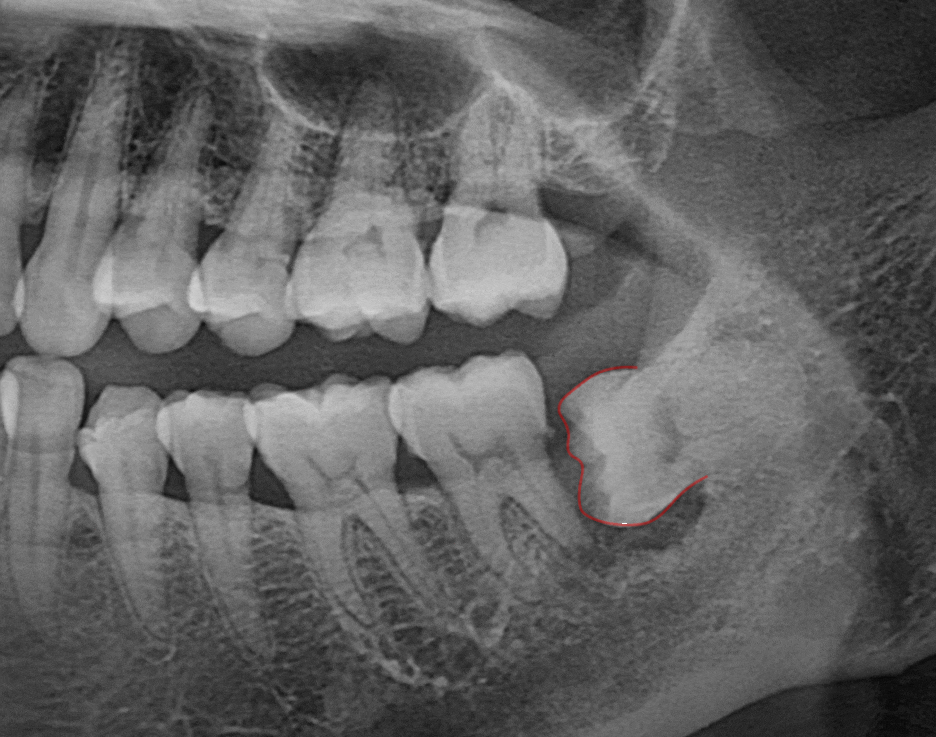

민락 치과 에서 표시한 부위를 보면

치아가 잇몸 안쪽으로 매복되어 있습니다.

실제로 CT 사진에서도

검게 보이는 영역이 관찰됩니다.

이는 방사선이 많이 통과되었다는 뜻으로

염증 반응 및 골소실을 의미합니다.

민락 치과 에서 확인한

제일 큰 문제는 염증의 범위입니다.

앞쪽 어금니에 확산된 모습으로,

원심 뿌리의 골소실이 큽니다.